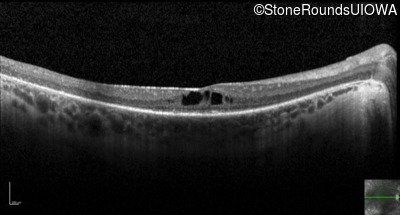

Optical Coherence Tomography - Right - 20/80 +2

Exemplar / OCT Stack